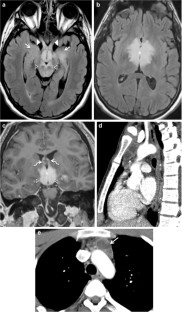

Fig. 3